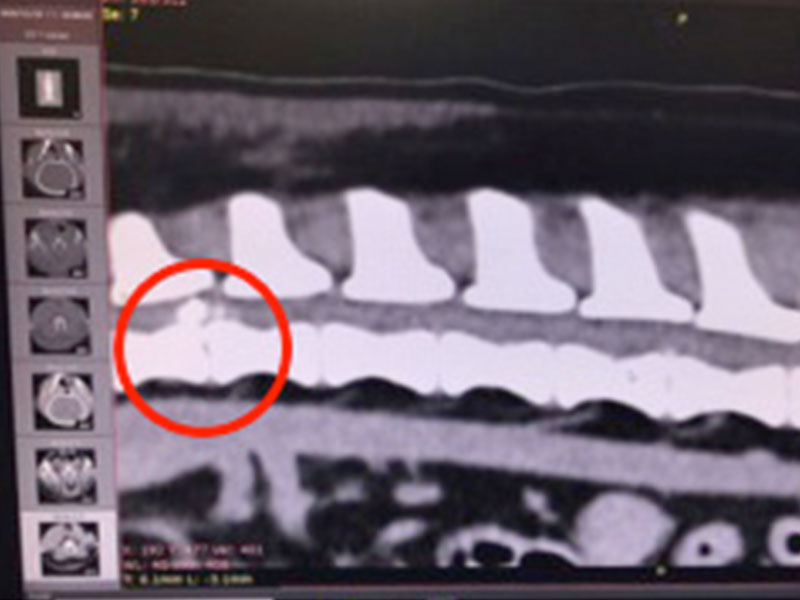

小胖主人發現後盡快將小胖帶來本院就診,經檢查後發現胖胖疑似脊髓問題導致的後肢突然癱瘓,當下仍有深層痛覺。

經過電腦斷層掃描(CT)後,發現在胸腰椎交界處的脊髓受到脫出的椎間盤物質壓迫,應為造成小胖後肢突然無法站立的主因,於是盡快安排手術將脫出物質取出,降低脊髓壓力。